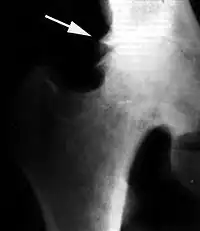

Рентгенологическая семиотика остеоартроза складывается из признаков, отражающих дистрофические изменения в суставных хрящах (сужение суставной щели) и в костной ткани (уплощение и деформация суставных поверхностей, кистовидные образования), нестабильность суставов (подвывихи, искривления оси конечностей), реактивные компенсаторно-приспособительные процессы (краевые костные разрастания, субхондральный остеосклероз).

Ранним рентгенологическим симптомом являются краевые костные разрастания — остеофиты — следствие активной пролиферации периферических отделов суставного хряща. Они проявляются вначале заострением краёв суставных поверхностей, а затем, нарастая, образуют массивные костные шипы и губы. Краевые остеофиты, как правило, раньше обнаруживаются со стороны суставных впадин.

Сужение суставной щели свидетельствует о значительных изменениях суставных хрящей. Суставная щель может стать клиновидной, суживаясь с одной стороны и нередко расширяясь при этом с противоположной, что указывает на недостаточность связочного аппарата и нестабильность сустава.

При остеоартрозе утрачивается амортизационная функция суставных хрящей, предохраняющих костную ткань от механических перегрузок. Как компенсация развивается остеосклероз субхондральной губчатой кости. Особенно он выражен при коксартрозе в крыше вертлужной впадины, распространяясь иногда почти на всё тело подвздошной кости. Однако рано или поздно этот механизм компенсации становится недостаточным. Механические силы, передающиеся непосредственно с одной суставной поверхности на другую, вызывают атрофию от давления их наиболее нагружаемых участков и прежде всего центральных отделов суставных головок. Вследствие этого они уплощаются и одновременно расширяются.

Результатом поражения суставных хрящей являются очаговые дистрофические и некротические процессы в субхондральной губчатой кости, соответствующие локальным пикам механических напряжений. В результате этих процессов формируются кистовидные образования. Последние наиболее характерны для коксартроза, при котором они часто множественны и достигают больших размеров (эрозивный артроз).

Рентгенологическое исследование играет важную роль в распознавании этиологических факторов при вторичных остеоартритах. Так, при посттравматическом остеоартрозе оно даёт возможность обнаружить костные деформации после внутрисуставных переломов, установить характерные признаки диспластических артрозов, особенно в тазобедренном суставе, на рентгенограммах можно выявить краевые дефекты суставных поверхностей, остеопороз и атрофию костей при постартритических артрозах. С помощью рентгенографии можно установить связь между отдалёнными от суставов деформациями костей диспластической, посттравматической или иной природы. Например, угловое искривление оси длинной трубчатой кости, сопровождающимися изменениями условий нагрузки на суставы, и вторичным (статическим) остеоартрозом. Рентгенологическое исследование даёт возможность выявить такие причины артроза, как внутрисуставное тело при хондроматозе сустава[20].